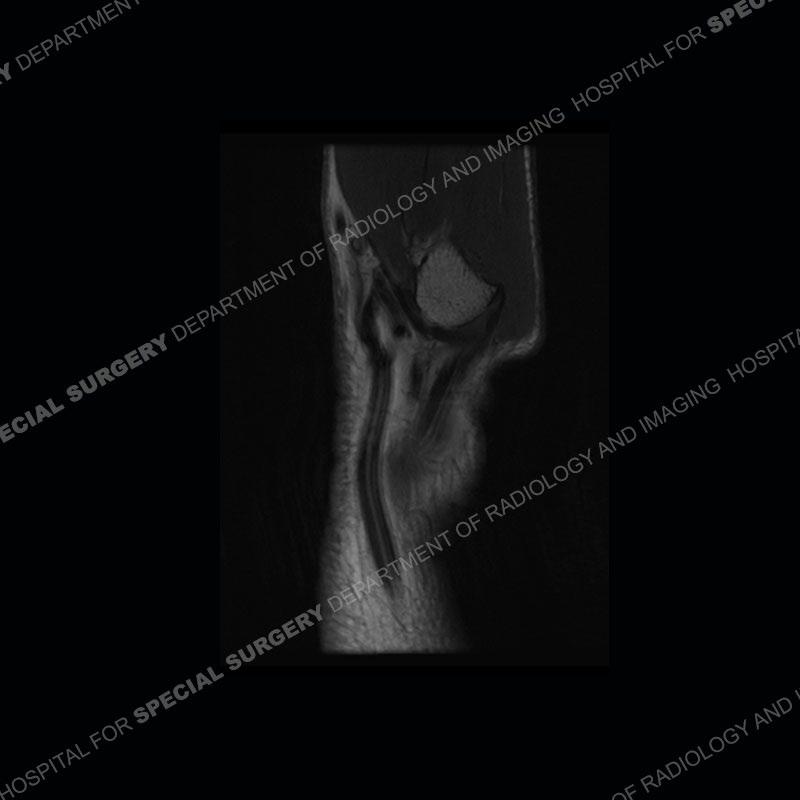

The radiographs in this case are not particularly contributory. The MRI demonstrates tenosynovitis of the first extensor compartment manifest by fluid/synovitis distention of the tendon sheaths. Multiple tendon slips are present of the abductor pollicis longus (APL) and with severe tendinosis seen of one of the tendon slips. Other areas of slightly increased signal and tendinosis are present of the components of the APL. Noted is a somewhat prominent septum separating the more dorsal extensor pollicis brevis (EPB) from the APL.

The first extensor compartment of the wrist contains the abductor pollicis longus or APL (slightly more volar) and the extensor pollicis brevis or EPB (slightly more dorsal). Tenosynovitis of this compartment is known by the eponym of DeQuervain’s tenosynovitis. In addition to tenosynovitis, tendinosis, and partial tearing can be seen. Complete disruption of the tendons is extremely uncommon. More common in women than men, this can affect almost any age patient. It is typically seen in individuals who perform repetitive gripping maneuvers or thumb overuse as can be seen in gripping a golf club or racket. The symptoms are frequently able to be managed with rest and ultrasound guided injections. Recalcitrant cases may require surgical intervention.